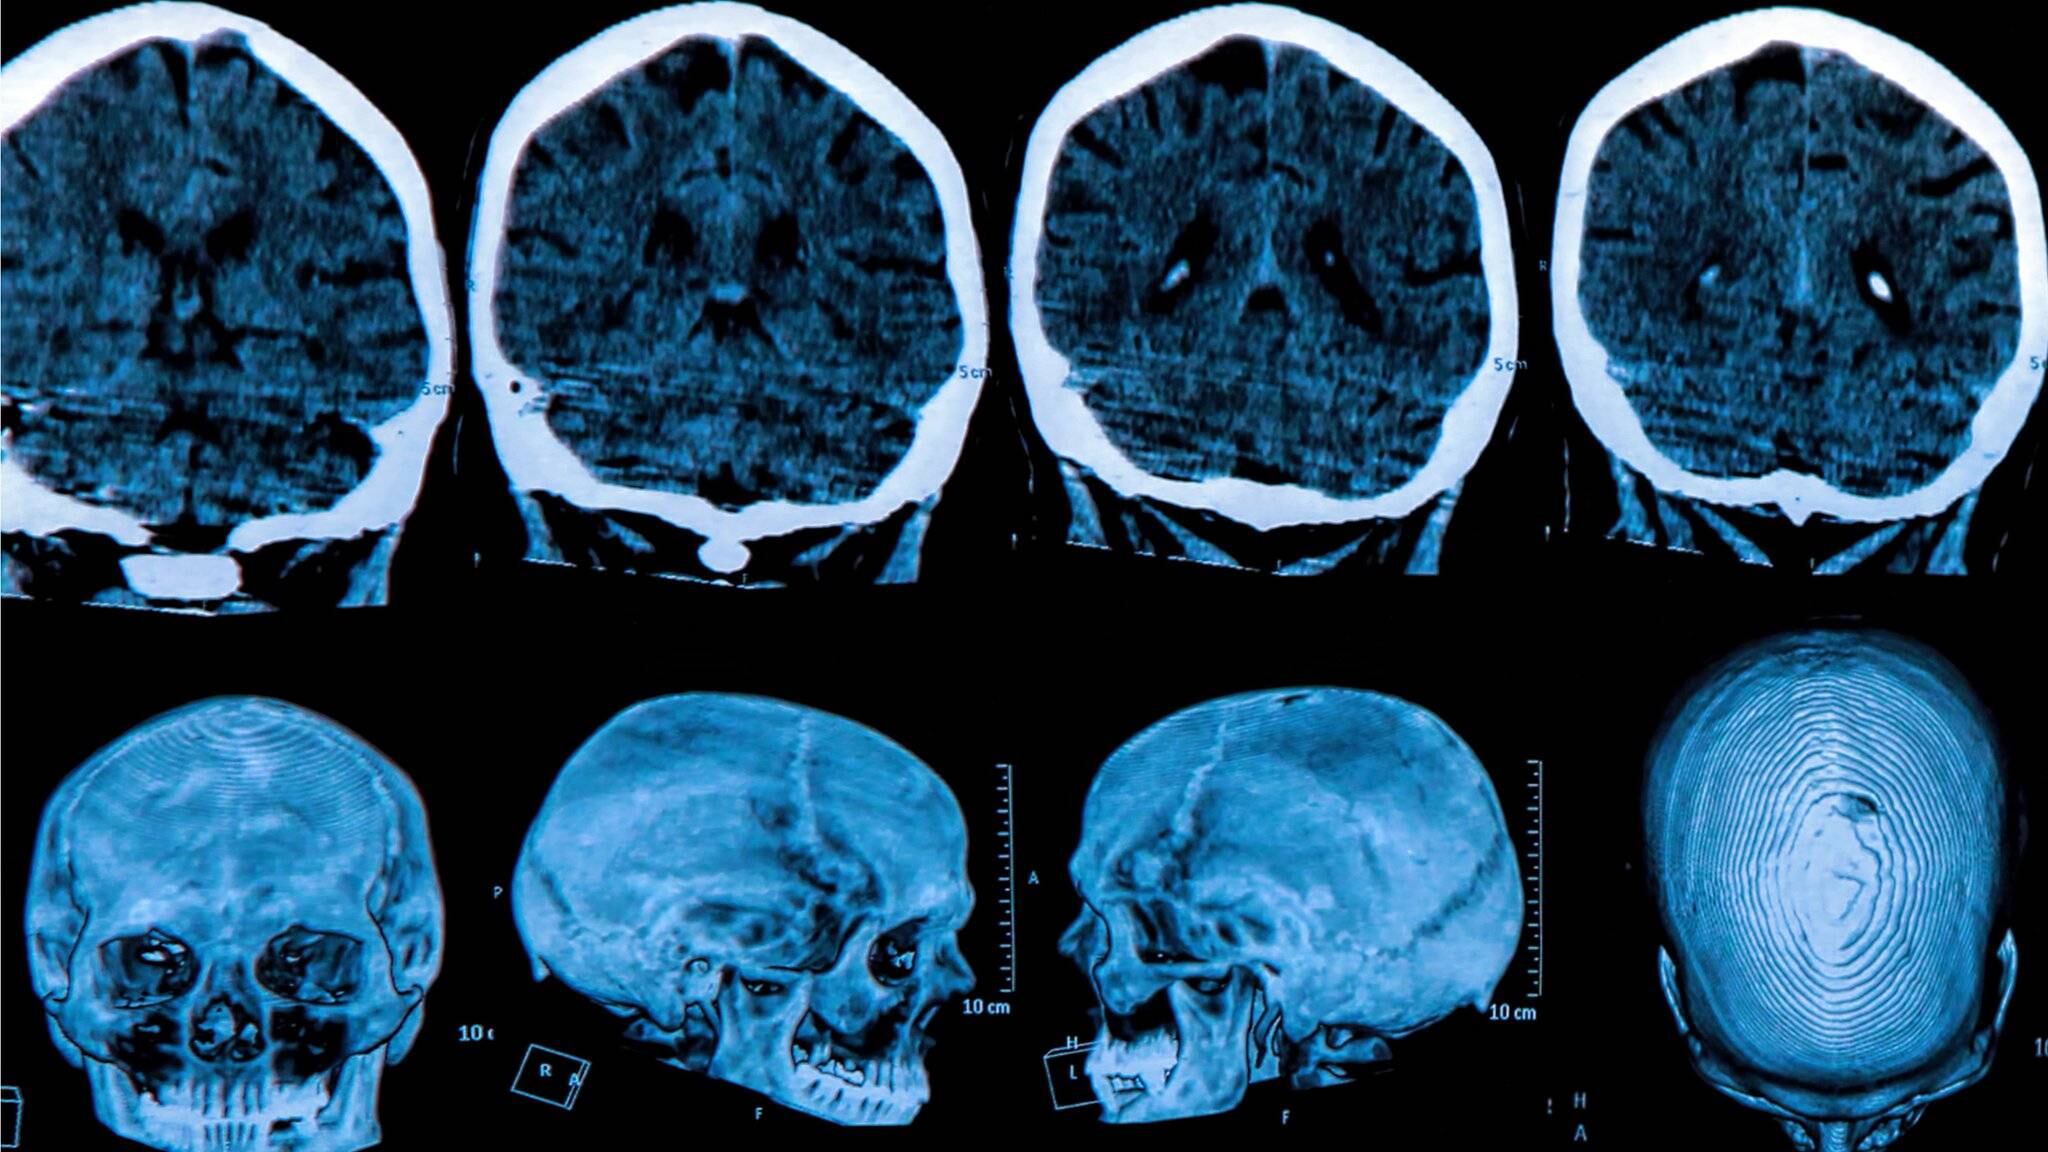

La enfermedad de Huntington es causada por un error en un pequeño tramo del ADN llamado gen de la huntingtina.

Generalmente, este contiene las instrucciones para crear la proteína huntingtina, que es vital para el desarrollo del cerebro.

Pero un error genético corrompe la proteína y la convierte en un asesino de las células cerebrales.